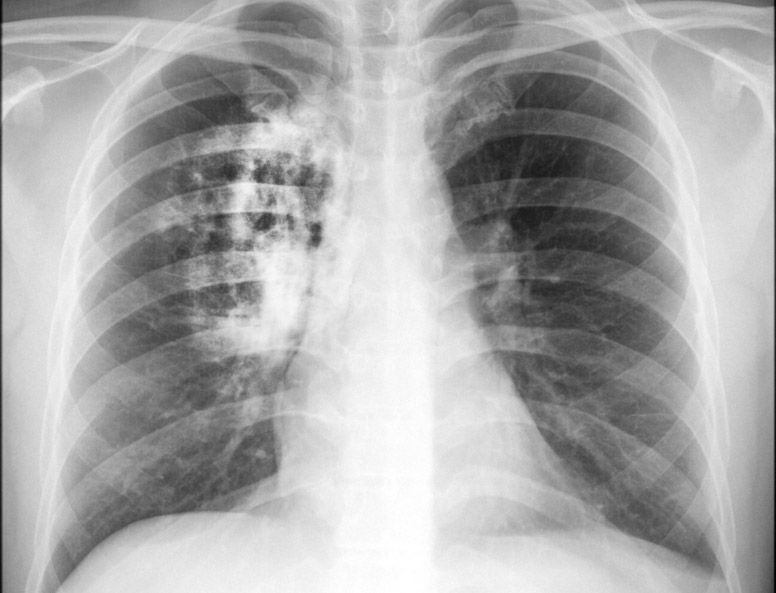

Como é feito o diagnóstico? Primeiramente é feito um raio X e se houver suspeita de câncer, ela será confirmada com uma biópsia. O oncologista afirma que não existe diagnóstico de câncer de pulmão sem biópsia. O procedimento pode ser tanto por broncoscopia, no qual um catéter é inserido pelo nariz ou pela boca do paciente até a árvore brônquica ou por biópsia guiada por tomografia por meio da parede torácica. As metástases podem ser biopsiadas com uma técnica chamada de imunohistoquímica, que confirma que a origem da metástase foi o câncer de pulmão.